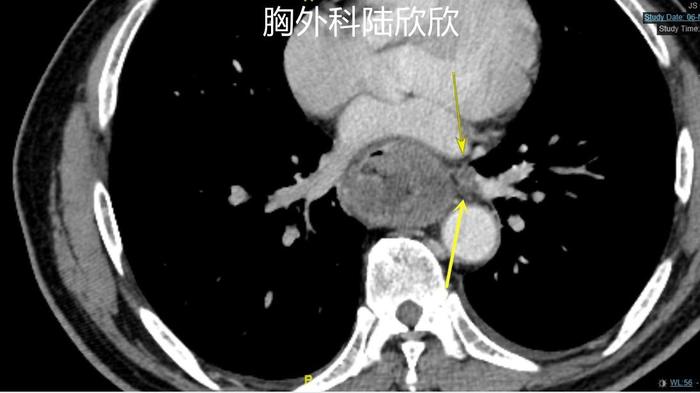

上图,心脏和脊柱间有巨大的软组织影,心脏被挤压变形。

上图,肿瘤周围的淋巴结,术后病理证实为转移淋巴结。只有这一个淋巴结发生转移。